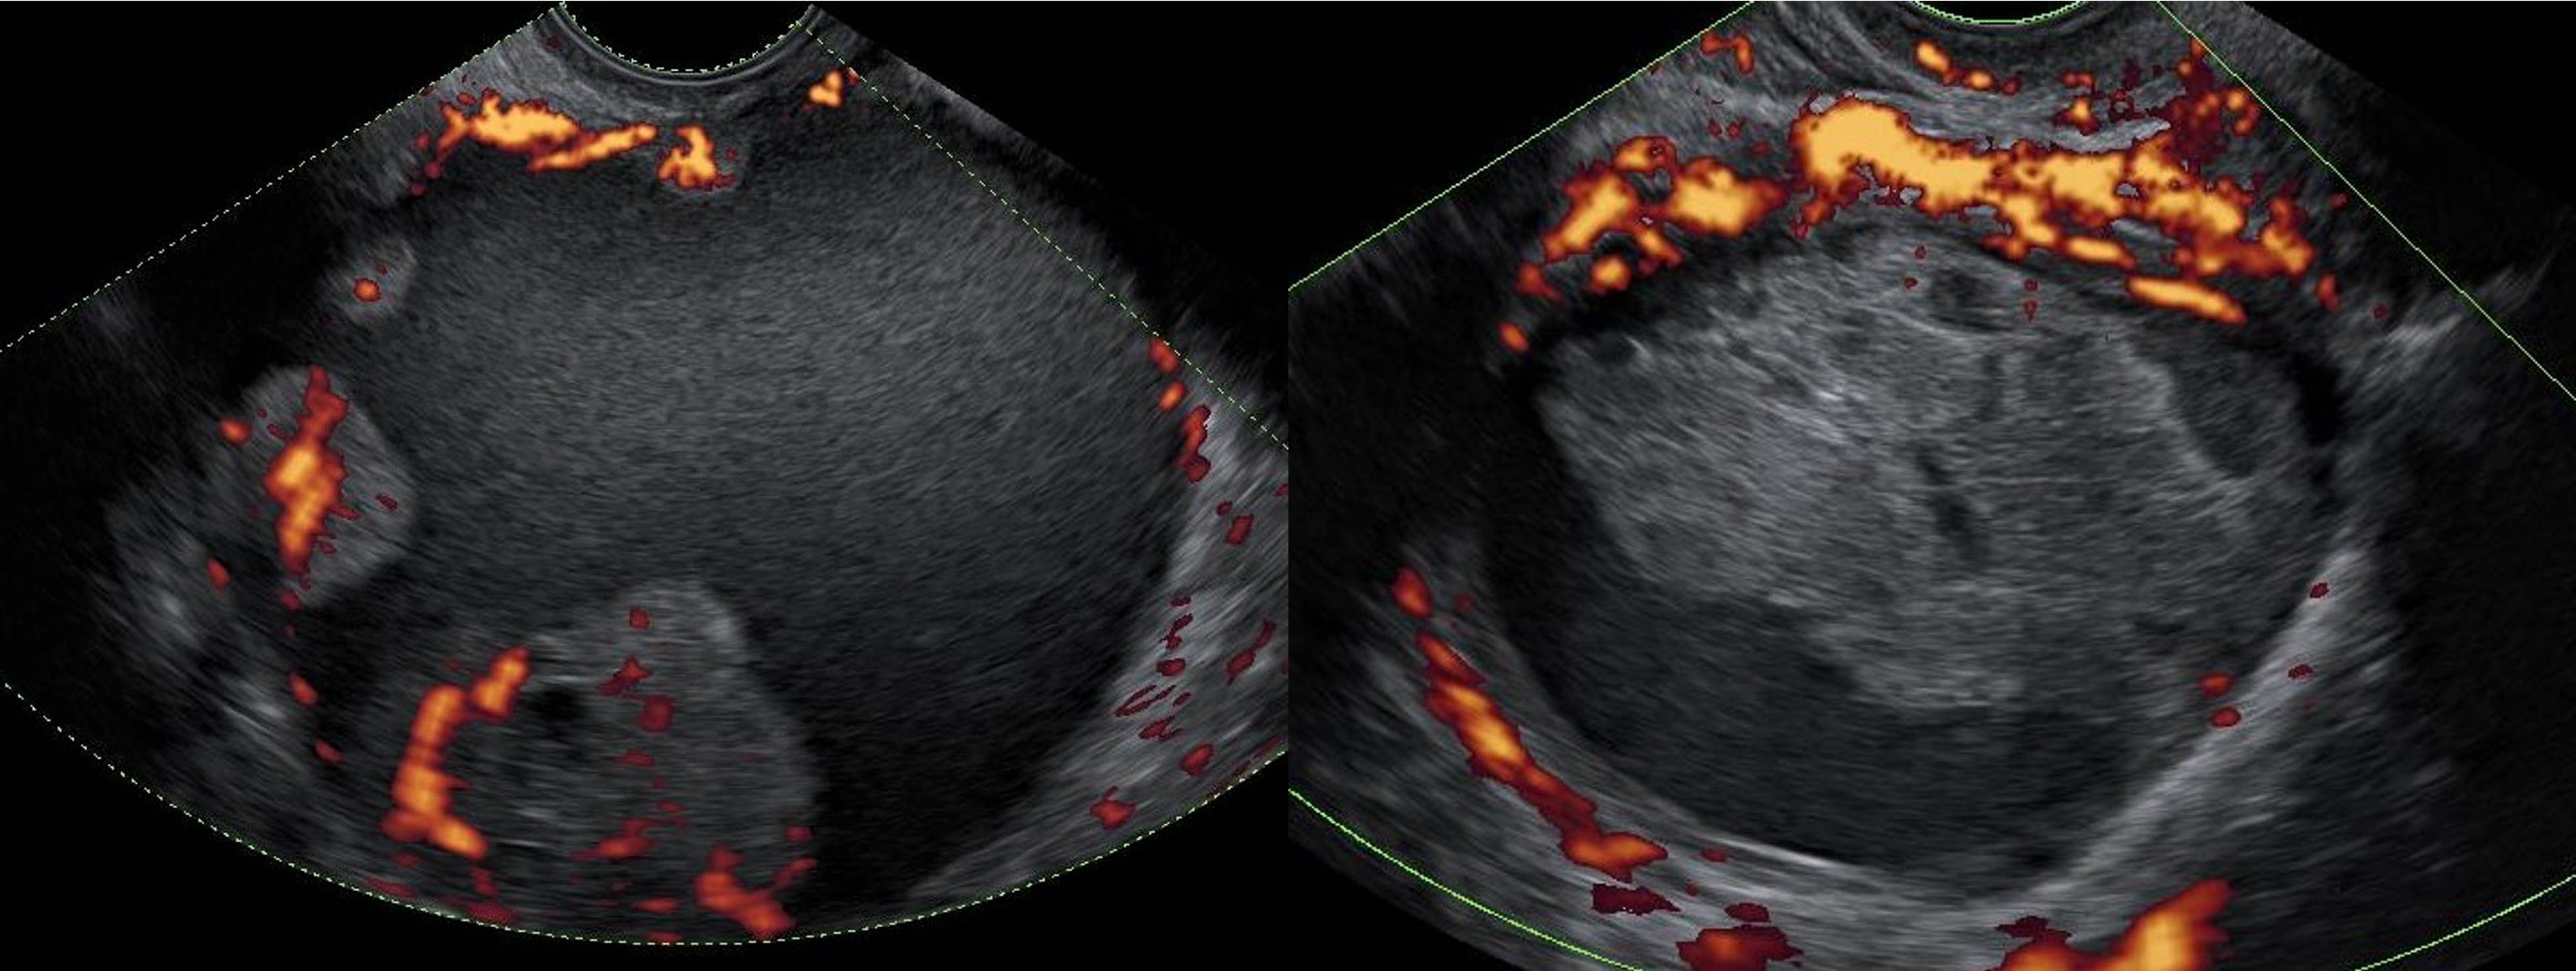

Ultrasound images of two ovarian lesionsâan ovarian cancer (left) and a benign functional lesion (right)âwith power Doppler visualizing their vascular activity.